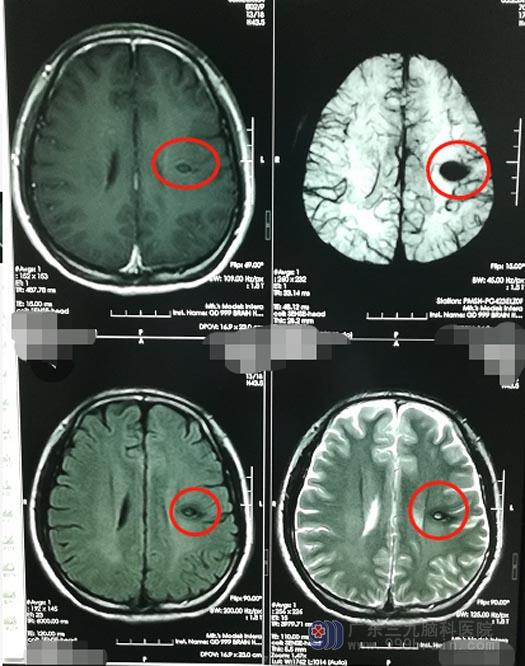

父母不愿意儿子的余生就这么度过,他们想着,现代科技都这么发达了,总会有好的办法解决儿子的问题。功夫不负有心人,通过多方收集信息,最后他们找着了广东三九脑科医院神经外五科。进一步头颅MR检查提示:左侧放射冠病灶,考虑为海绵状血管瘤。

医院副院长、神经外五科主任鲁明告诉他们,肿瘤的位置很深,毗邻周围重要结构,致使肿瘤全切除颇为困难,稍有不慎就会损伤颅内重要组织和神经,甚至可能会危及生命。神经外五科的治疗团队为李大哥制定了一套周密的手术方案,运用机器人辅助定位,定位更为精准能大大提高手术的成功率。